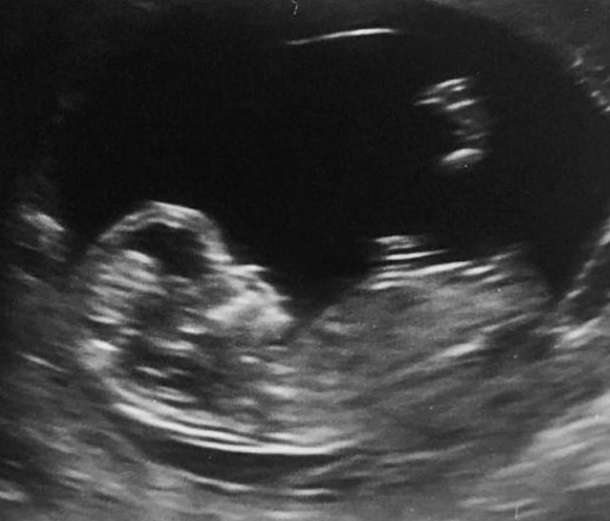

These are pics from my 12week+2 scan. I'm now 14+3 and dying to know.

Attachment 31108 Attachment 31109